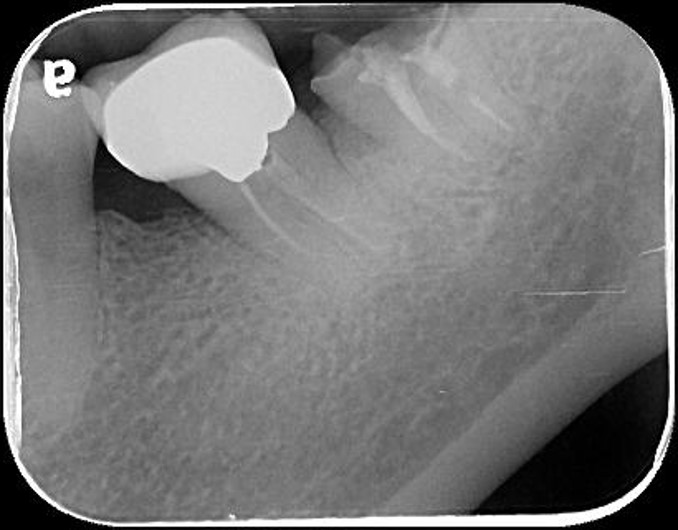

治療後X光再次檢查密合性